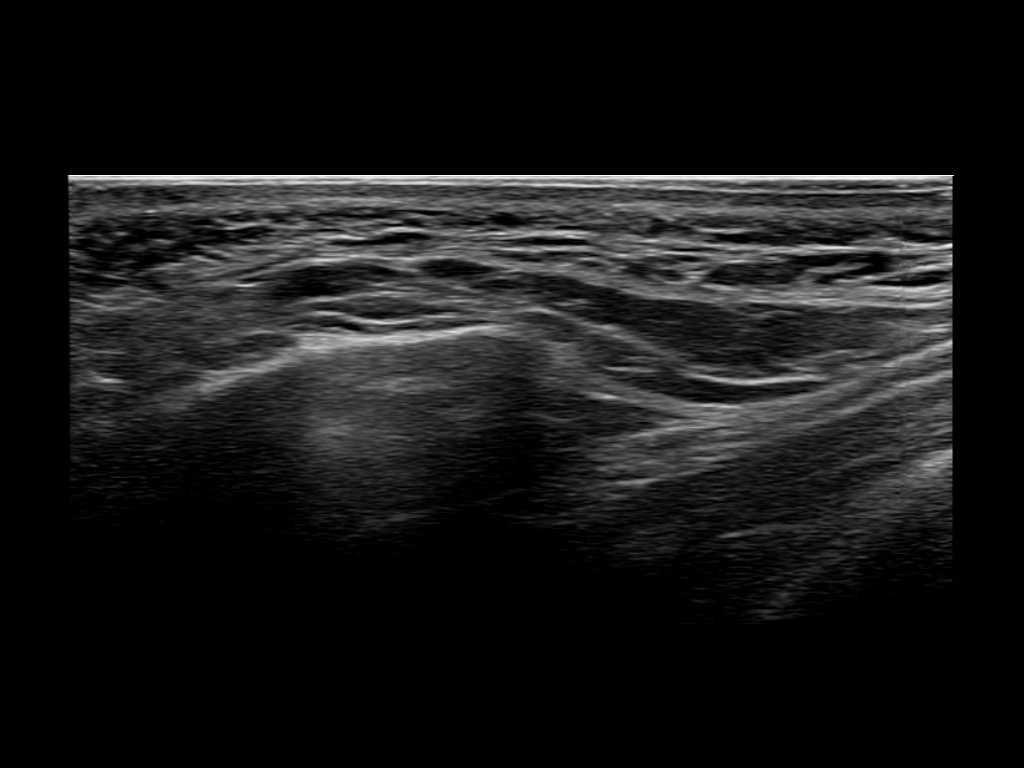

Study the first image to recognize the different layers. If you are sure about the layers, swipe to the second image to view the answer (if applicable).